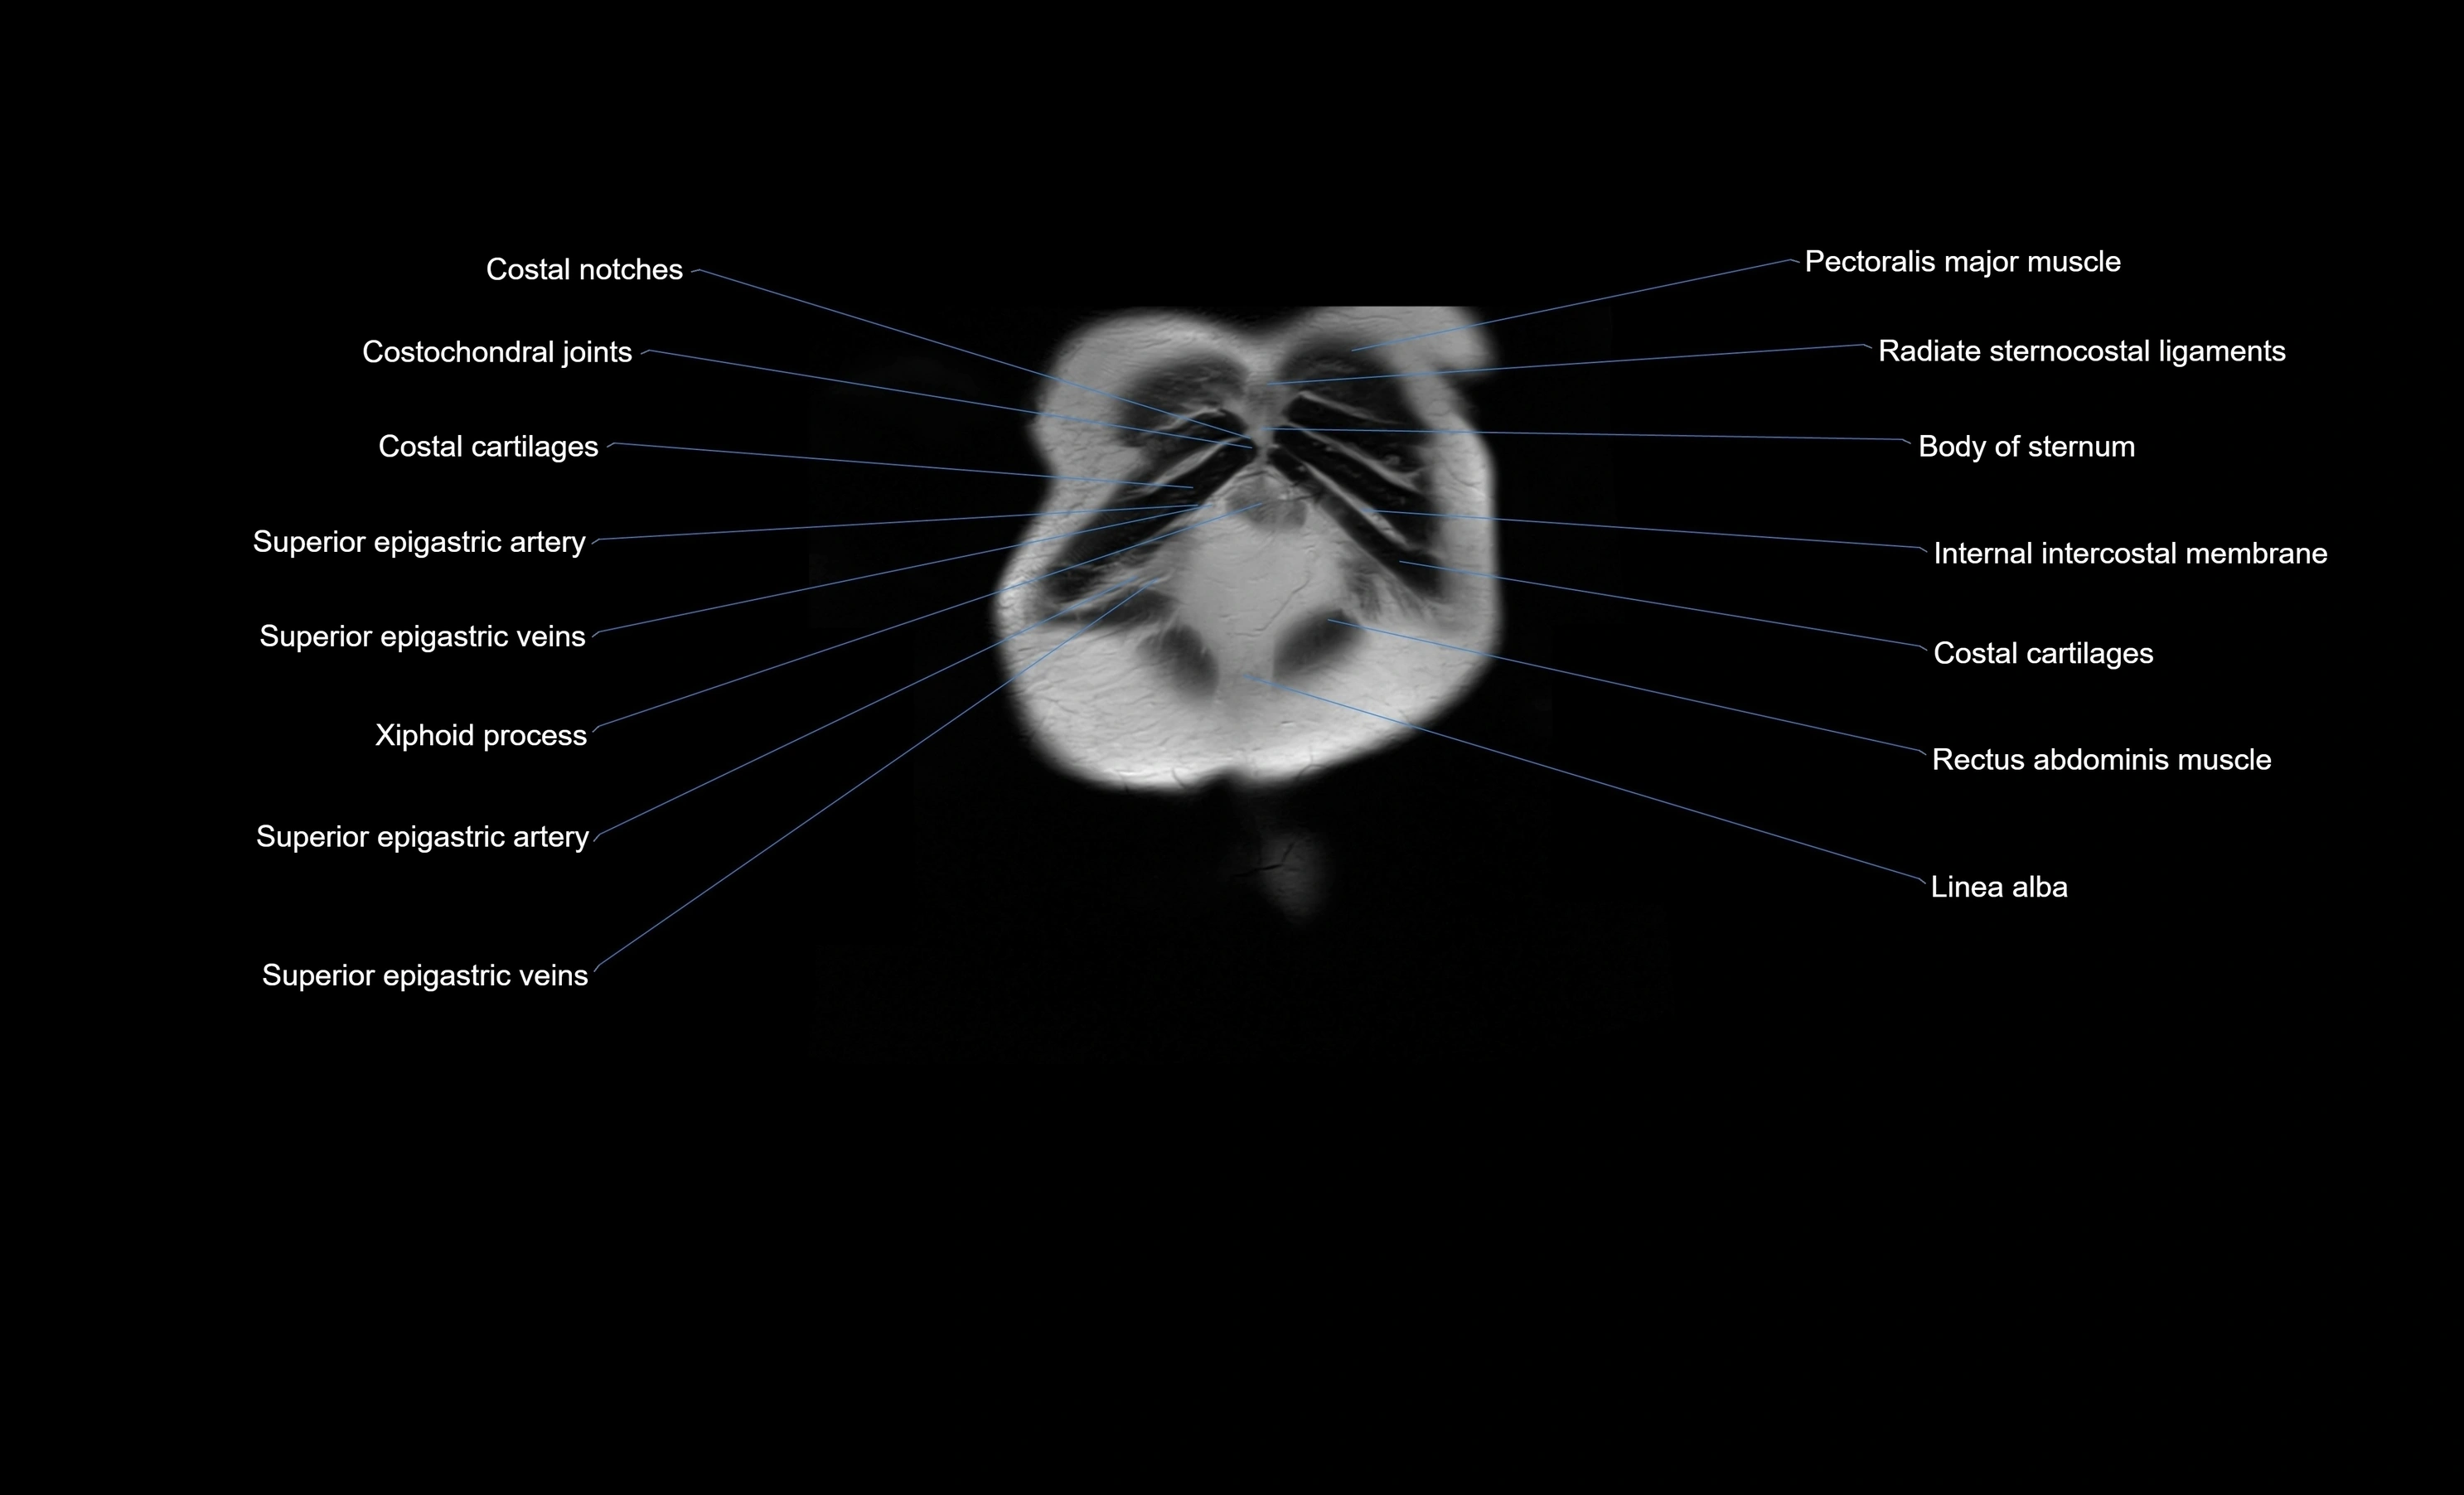

- Superior epigastric artery

- Superior epigastric veins

- Costochondral joints

- Rectus abdominis muscle

- Linea alba

- Transversus thoracis muscle